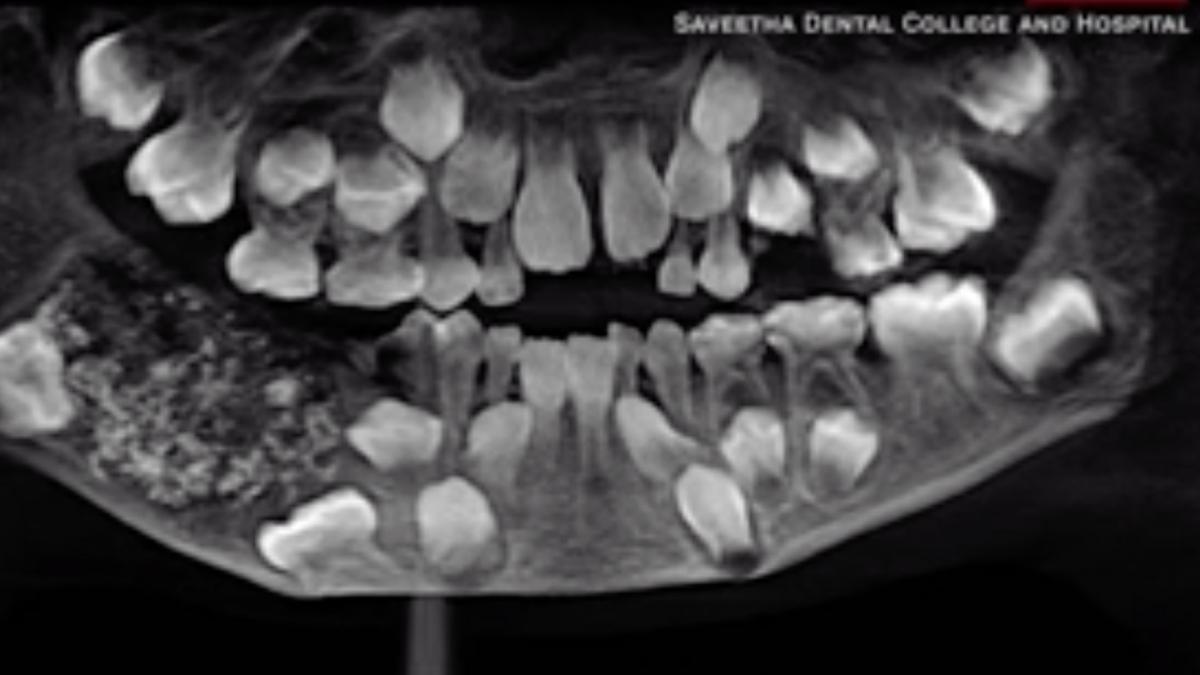

Medicii de la spitalul din oraşul Chennai, care au scanat şi radiografiat gura băiatului, au descoperit un "sac" în maxilarul său drept, plin cu dinţi "anormali", indicând că băiatul suferea de o afecţiune rară, numită odontom compus.

"Un total de 526 de dinţi, variind de la 0,1 milimetri la 15 milimetri au fost scoşi de echipa noastră. Toţi aveau coroană, rădăcină şi un strat de smalţ", a completat Ramani.

Operaţia de extracţie a dinţilor, care cântăreau în total 200 grame, a durat cinci ore.

Potrivit Ramani, acest caz este primul documentat la nivel mondial unde un număr atât de mare de dinţi a fost descoperit la un individ, după ce în 2014, medicii de la un spital din Mumbai au scos 232 de dinţi din maxilarul unui adolescent.

Operaţia s-a dovedit un succes, astfel că băiatul, rămas cu un număr "normal" de 21 de dinţi, a fost externat la trei zile după procedură.